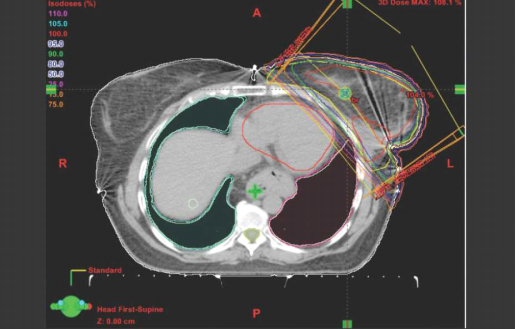

ניתן לרפא חלק ניכר מהנשים שלקו בסרטן שד, מבלי לפגוע בלב כתוצאה מהקרינה. עם זאת, לעיתים, כתוצאה מהתלות באנטומיה (תמונה מספר 1). היות שהלב נמצא במיקום קדמי (Anterior), מתן קרינה לשד ולמיקום הגידול המקורי מבלי להקרין חלק מהלב הוא בלתי אפשרי. במקרים כאלה יש לנסות לדחוק את הלב אחורנית (Posterior) ולהרחיקו מדופן בית החזה באמצעות נשימה עמוקה, שיכולה להזיזו משדה הטיפול למרחק של סנטימטר (ס"מ) וחצי לאחור, ולהוות חייץ המגן עליו (תמונה מספר 2).